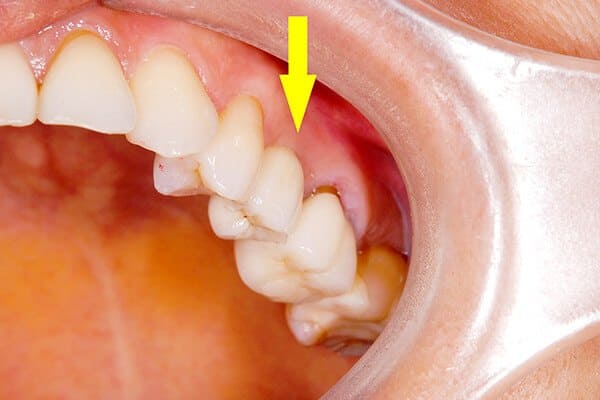

50代女性の症例

黄色矢印の歯がインプラントです

カスタムメイドアバットメントを連結、

セラミックの歯を装着する前